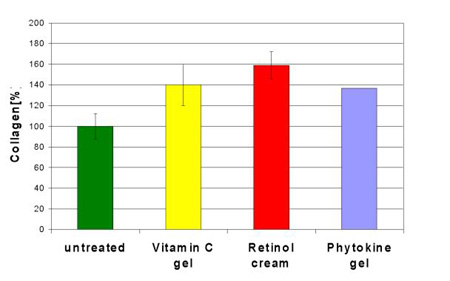

Ascorbinsäure (Vitamin C) ist ein Cofaktor für die Enzyme Lysylhydroxylase und Prolylhydroxylase, die beide essentiell für die Collagenbiosynthese sind. Im Hautmodell wurde aus diesem Grund in unseren Untersuchungen Vitamin C als Positivkontrolle gewählt. Die viermalige topische Anwendung eines Vitamin C-haltigen Gels (50 mg/l Ascorbinsäure) führte innerhalb von 10 Tagen zu einer Steigerung der Gesamt-Collagenproduktion um 40% im Vergleich zur unbehandelten Kontrolle. Für stabilisiertes Retinol, als 0,024%ige kommerzielle Creme über 10 Tage viermal angewendet, wurde eine Steigerung der Collagensynthese um 59% gefunden (5). Retinol wirkt damit ähnlich stimulierend wie Retinsäure, deren Wirksamkeit in mehreren Studien sowohl in vitro (11) als auch in vivo (9,12) nachgewiesen worden ist. Im Unterschied zu Retinsäure ist Retinol wesentlich weniger hautirritierend (13) und führte in verkapselter Form in der eingesetzten kosmetischen Creme zu keiner Hautirritation.

Interessanterweise sind auch manche aus Pflanzen gewonnen Extrakte in der Lage, diese cytokinartige Wirkung zu entfalten (15). So führt Phytokine , ein Sojapeptid, nach 2-wöchiger topischer Anwendung aus einer 10%igen Gelformulierung zu eine Steigerung der Collagensynthese um 37% (16). Abgebautes Collagen kann so in der gealterten Haut ersetzt werden, wie in einer in vivo Studie gezeigt werden konnte (16). In Abb. 3 sind die Ergebnisse zusammenfassend dargestellt.

Abb. 3: Stimulierung der Collagensynthese durch ein 0,005%iges Vitamin C-Gel , eine kommerziell erhältliche Retinolcreme (0,024% Retinol) und ein 10%iges Phytokine -Gel im Ganzhautmodell (Mittelwerte SD aus (5) und (16) zusammengestellt).